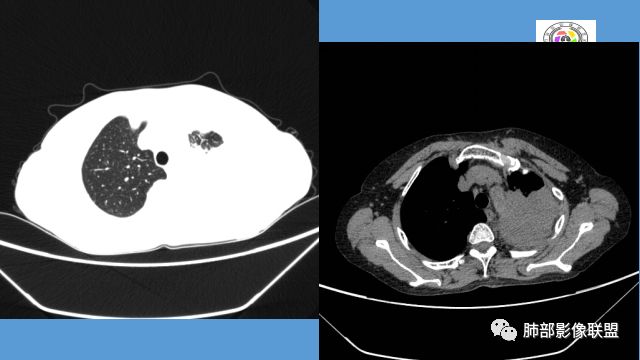

左肺团块影,形态不规则,其内见充气支气管征,增强扫描明显强化,其内见液化坏死区。下叶基底段见斑点状密度增高影。双肺门见斑点状钙化影。疾病谱有结核,增强除外了。肺癌和淋巴瘤鉴别。

病灶远端有扩张支气管,树芽,实变,纵隔肺内淋巴结钙化,考虑肺结核。

左肺占位,边界平直,无明显膨胀性,炎性首先考虑,支气管壁不光滑,考虑气道来源,青年女性,有地热,乏力,体重减轻,结合病灶周围有树芽征,我考虑结核!

整个上叶尖后段阻塞性肺不张的表现,从强化来看没有异常结节状或肿块样强化,肿块内部点状钙化、纵隔多发小淋巴结、下叶背段有树芽征,整体来看支持肺结核,让人不放心的是最后一幅冠状位重建的图像尖后段支气管堵了,而且有轻度的隆起,所以很难除外粘液表皮样癌(女性,鳞癌可能性小),如果是我写报告肯定会建议纤支镜检查

中年女性,反复咳嗽咳痰4月,加重半月,咳嗽,咳黄痰。胸CT:左肺体积缩小,左肺上叶病变,病灶内可见支气管征,病灶边缘可见棘突样改变,病灶周围可见结节状卫星灶,纵隔可见淋巴结肿大,部分淋巴结可见钙化灶。增强CT病灶内可见低密度坏死区,冠状位病灶内支气管可见扩张,病灶整体呈收缩,考虑患者为良性慢性感染性病变,结核?放线?,建议支气管镜检查。

中年女性,反复咳嗽咳痰4月。胸CT:左肺上叶块状病变,病灶内可见支气管征,边缘见棘突样改变,周围可见结节状卫星灶,纵隔可见淋巴结肿大,部分淋巴结可见钙化灶。增强CT病灶内可见低密度坏死区。病灶整体呈收缩,考虑为良性病变,结核可能性大,建议支气管镜检查。